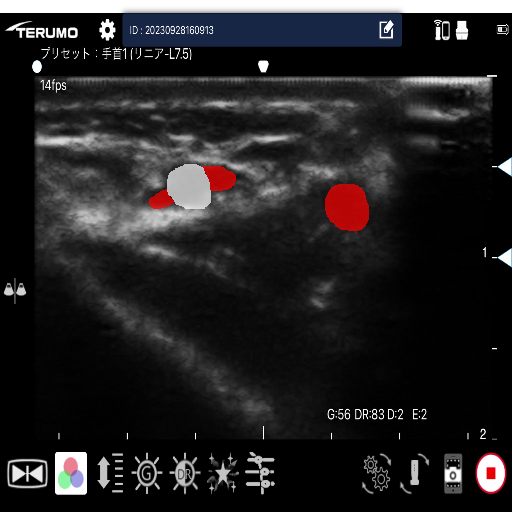

医療現場において、エコー穿刺等の手技によって超音波動画像が活用されています。エコー穿刺は、穿刺部位に超音波を当て、動画像からリアルタイムで血管の位置を確認しながら、動脈もしくは静脈に穿刺を実施する方法です。

しかし、超音波動画像は不明瞭な上、動脈と静脈の見分けを時系列的な血管の形状変化で判断する必要があり、熟練者でなければ判断が難しい現状があります。

現在、動脈及び静脈を含む超音波動画像から動画像解析を活用した機械学習モデルの学習・推論を行い、その分類精度の評価を行なっています。

超音波動画像からの動脈・静脈検出